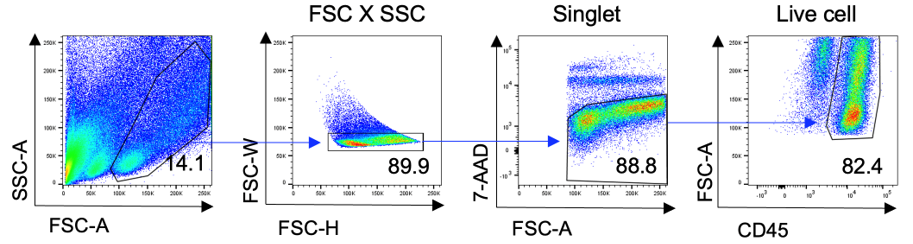

신경면역학 실험실(Neuroimmunology Laboratory)은 신경계와 다양한 말초조직 간의 상호작용을 연구합니다. 특히 말초조직 또는 면역세포를 조절하는 자율신경 신경회로를 발굴하고 작용기전을 밝힘으로써, 대사장애, 만성 염증성 질환, 종양, 근감소증 등을 극복하는 연구를 수행합니다.

신경계-면역계 상호작용 연구

- 연구주제 : 비만 및 대사장애 발생을 조절하는 신경계-면역계 상호작용 연구